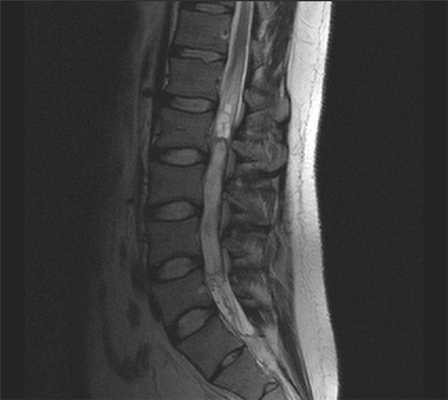

В первом учреждении использовался локатор на весь позвоночник, Т1-, Т2-, STIR-взвешенные изображения в сагиттальной плоскости, Т2-взвешенные изображения в коронарной плоскости (рис. 1). Исследование выполнялось на аппарате Рhilips Intera 1.5Т. Технические параметры импульсных последовательностей представлены в таблице. Технические параметры импульсных последовательностей для МРТ поясничного отдела позвоночника

Рис. 1. МРТ поясничного отдела позвоночника, позиционирование плоскостей. а — позиционирование локатора на весь позвоночник; б — позиционирование сагиттальной плоскости.